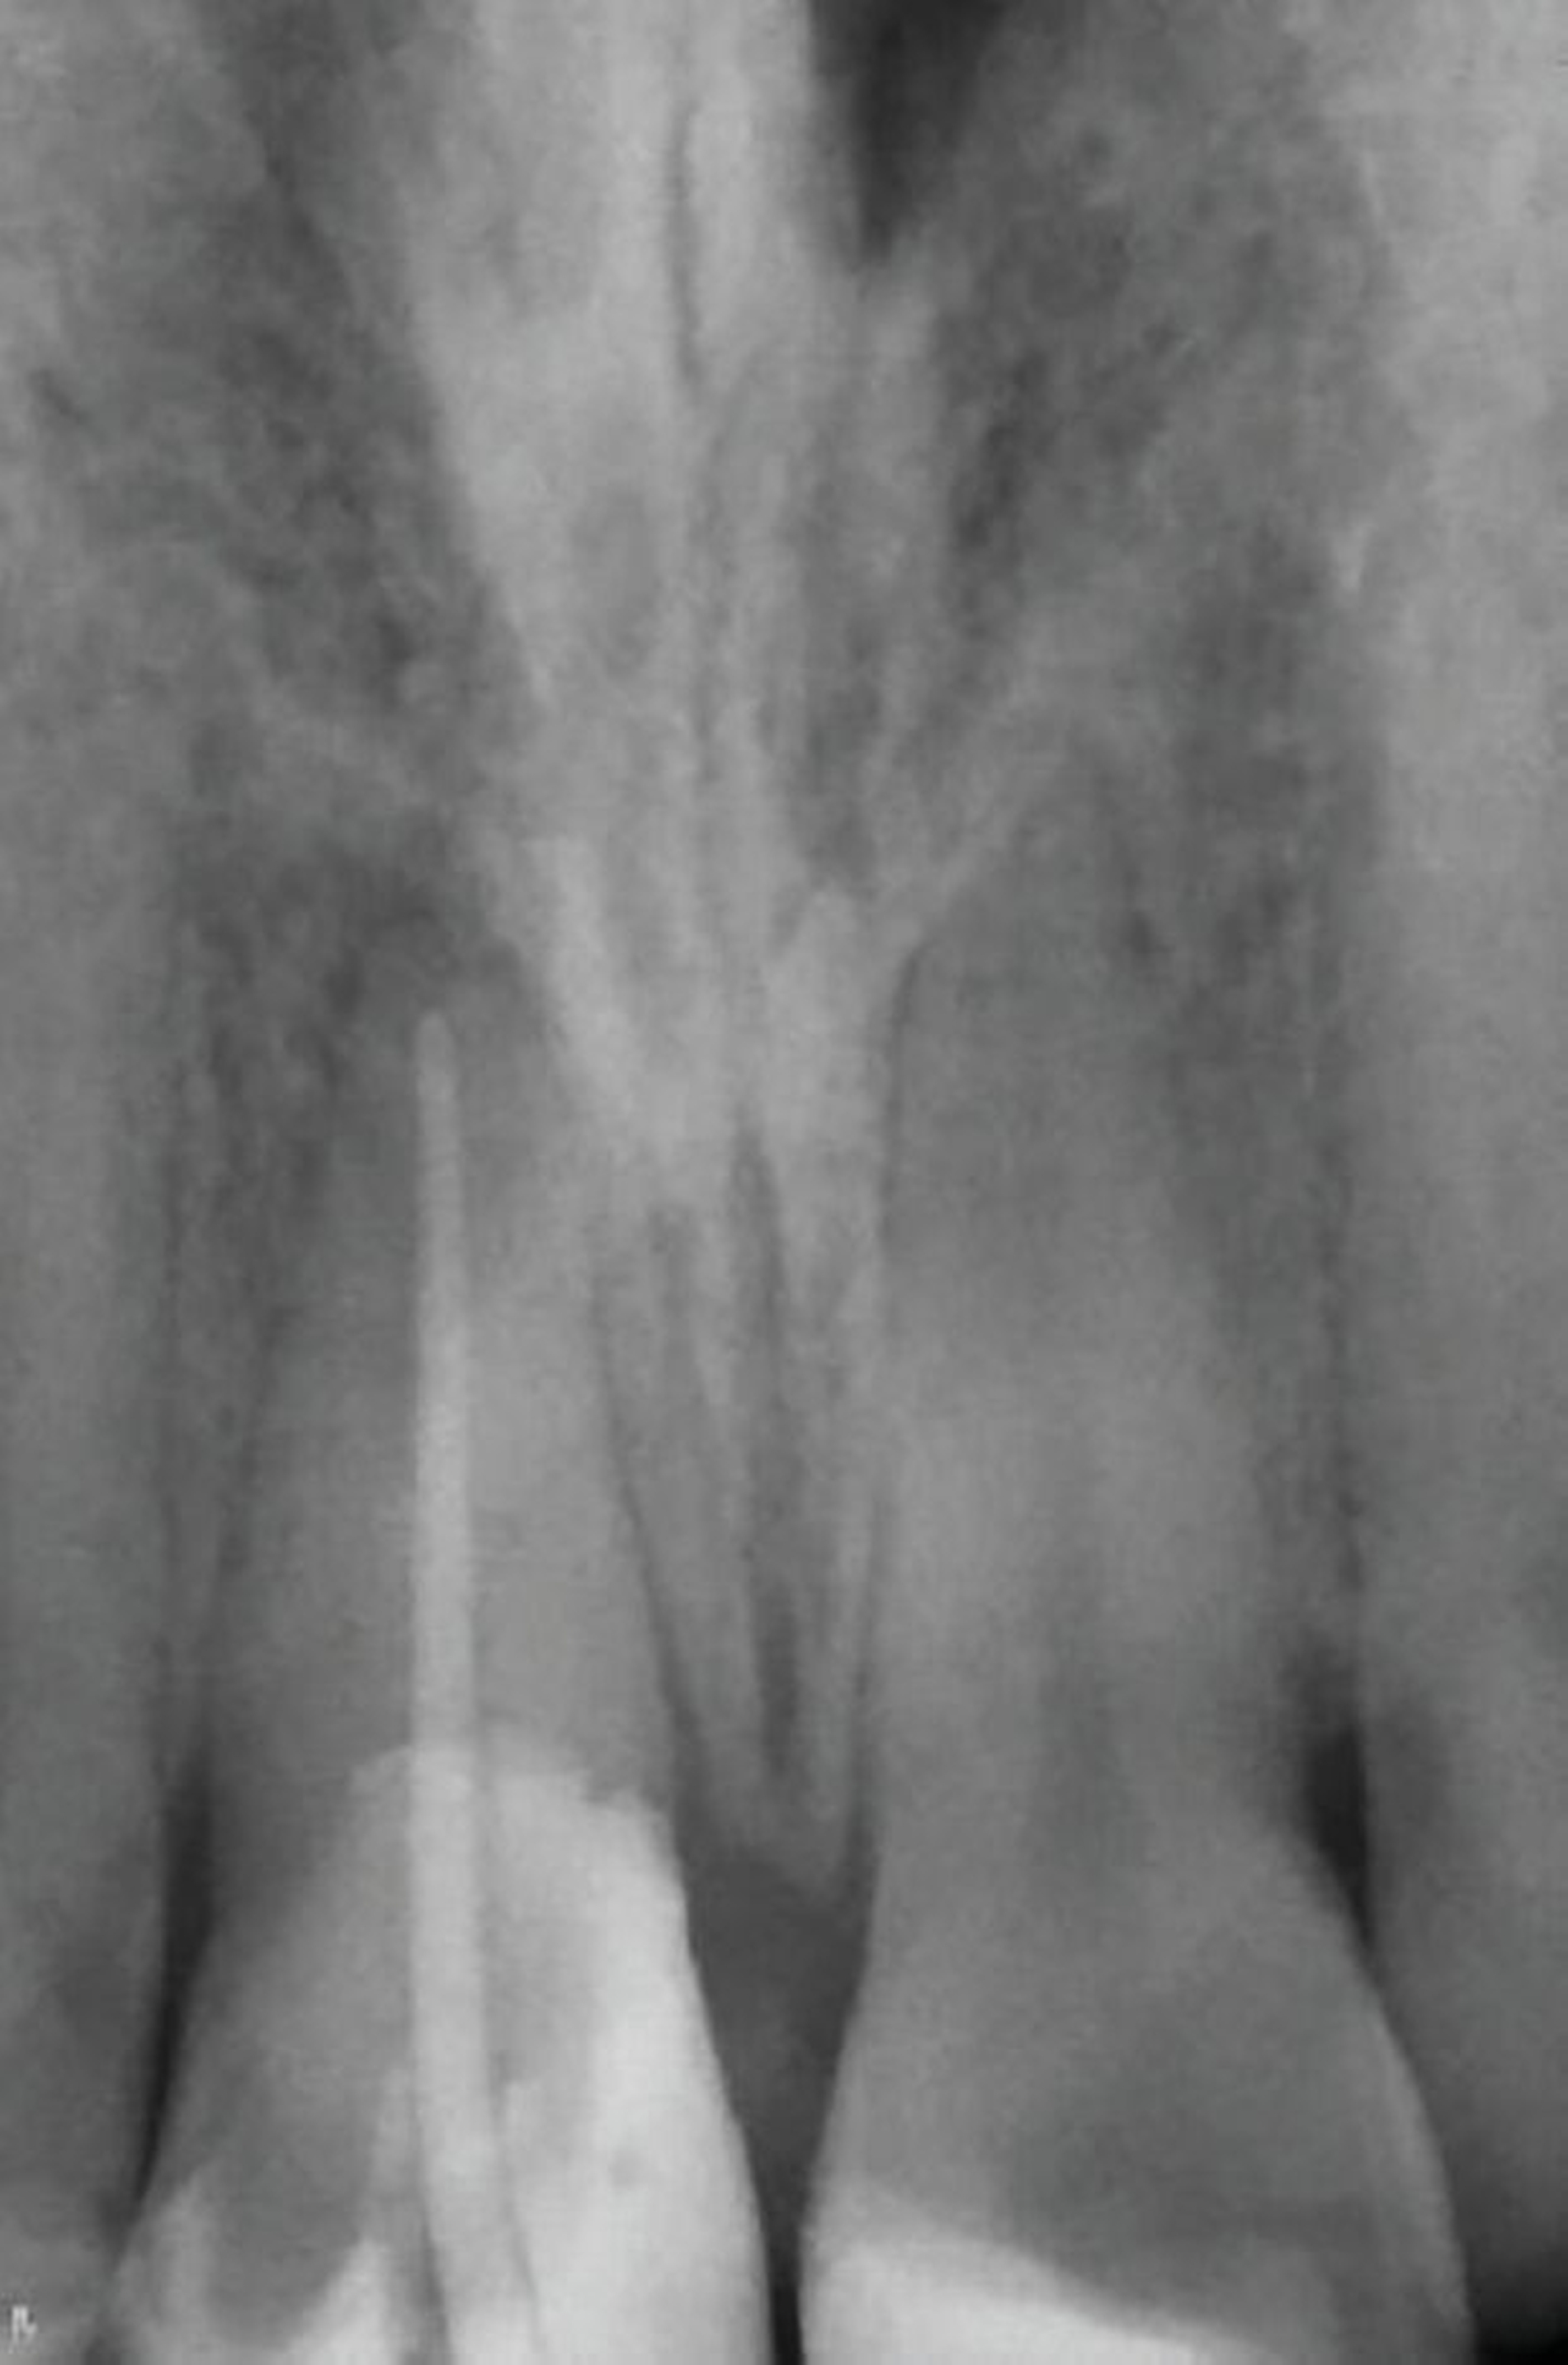

Ein 22-jähriger Patient stellte sich im Februar 2020 im zahnärztlichen Notdienst der Klinik für Zahn-, Mund- und Kieferkrankheiten Mainz vor. Aufgrund einer Synkope war er mit dem Oberkiefer auf den Rand einer Badewanne gestürzt. Intraoral zeigte sich der Zahn 12 mit einer Schmelz-Dentin-Fraktur ohne Pulpabeteiligung (unkomplizierte Kronenfraktur), der Zahn 11 mit einer Kronen-Wurzel-Fraktur mit Pulpabeteiligung und der Zahn 21 mit einer Schmelz-Dentin-Fraktur mit Pulpabeteiligung (komplizierte Kronenfraktur). Die Zähne zeigten keine erhöhten Lockerungsgrade oder Dislokationen (Abbildung 2). Herausfordernd für die weitere Versorgung war der Frakturverlauf an Zahn 11, an dem die Frakturkante palatinal tief subgingival und mesio-palatinal auch subkrestal lag. Röntgenologisch konnte die klinisch gestellte Verdachtsdiagnose bestätigt und eine Wurzelfraktur ausgeschlossen werden (Abbildung 3).

In der zwischenzeitlich angefertigten Einzelzahnaufnahme sind die orthopädisch bedingten Umbauprozesse anhand eines deutlich erweiterten Parodontalspalts und an der Verlagerung des Zahnes nach koronal zu erkennen (Abbildung 13). Auffällig ist, dass approximal ein Knochenumbau stattgefunden hat, was im Rahmen der kieferorthopädischen Extrusionstherapie zu erwarten war.